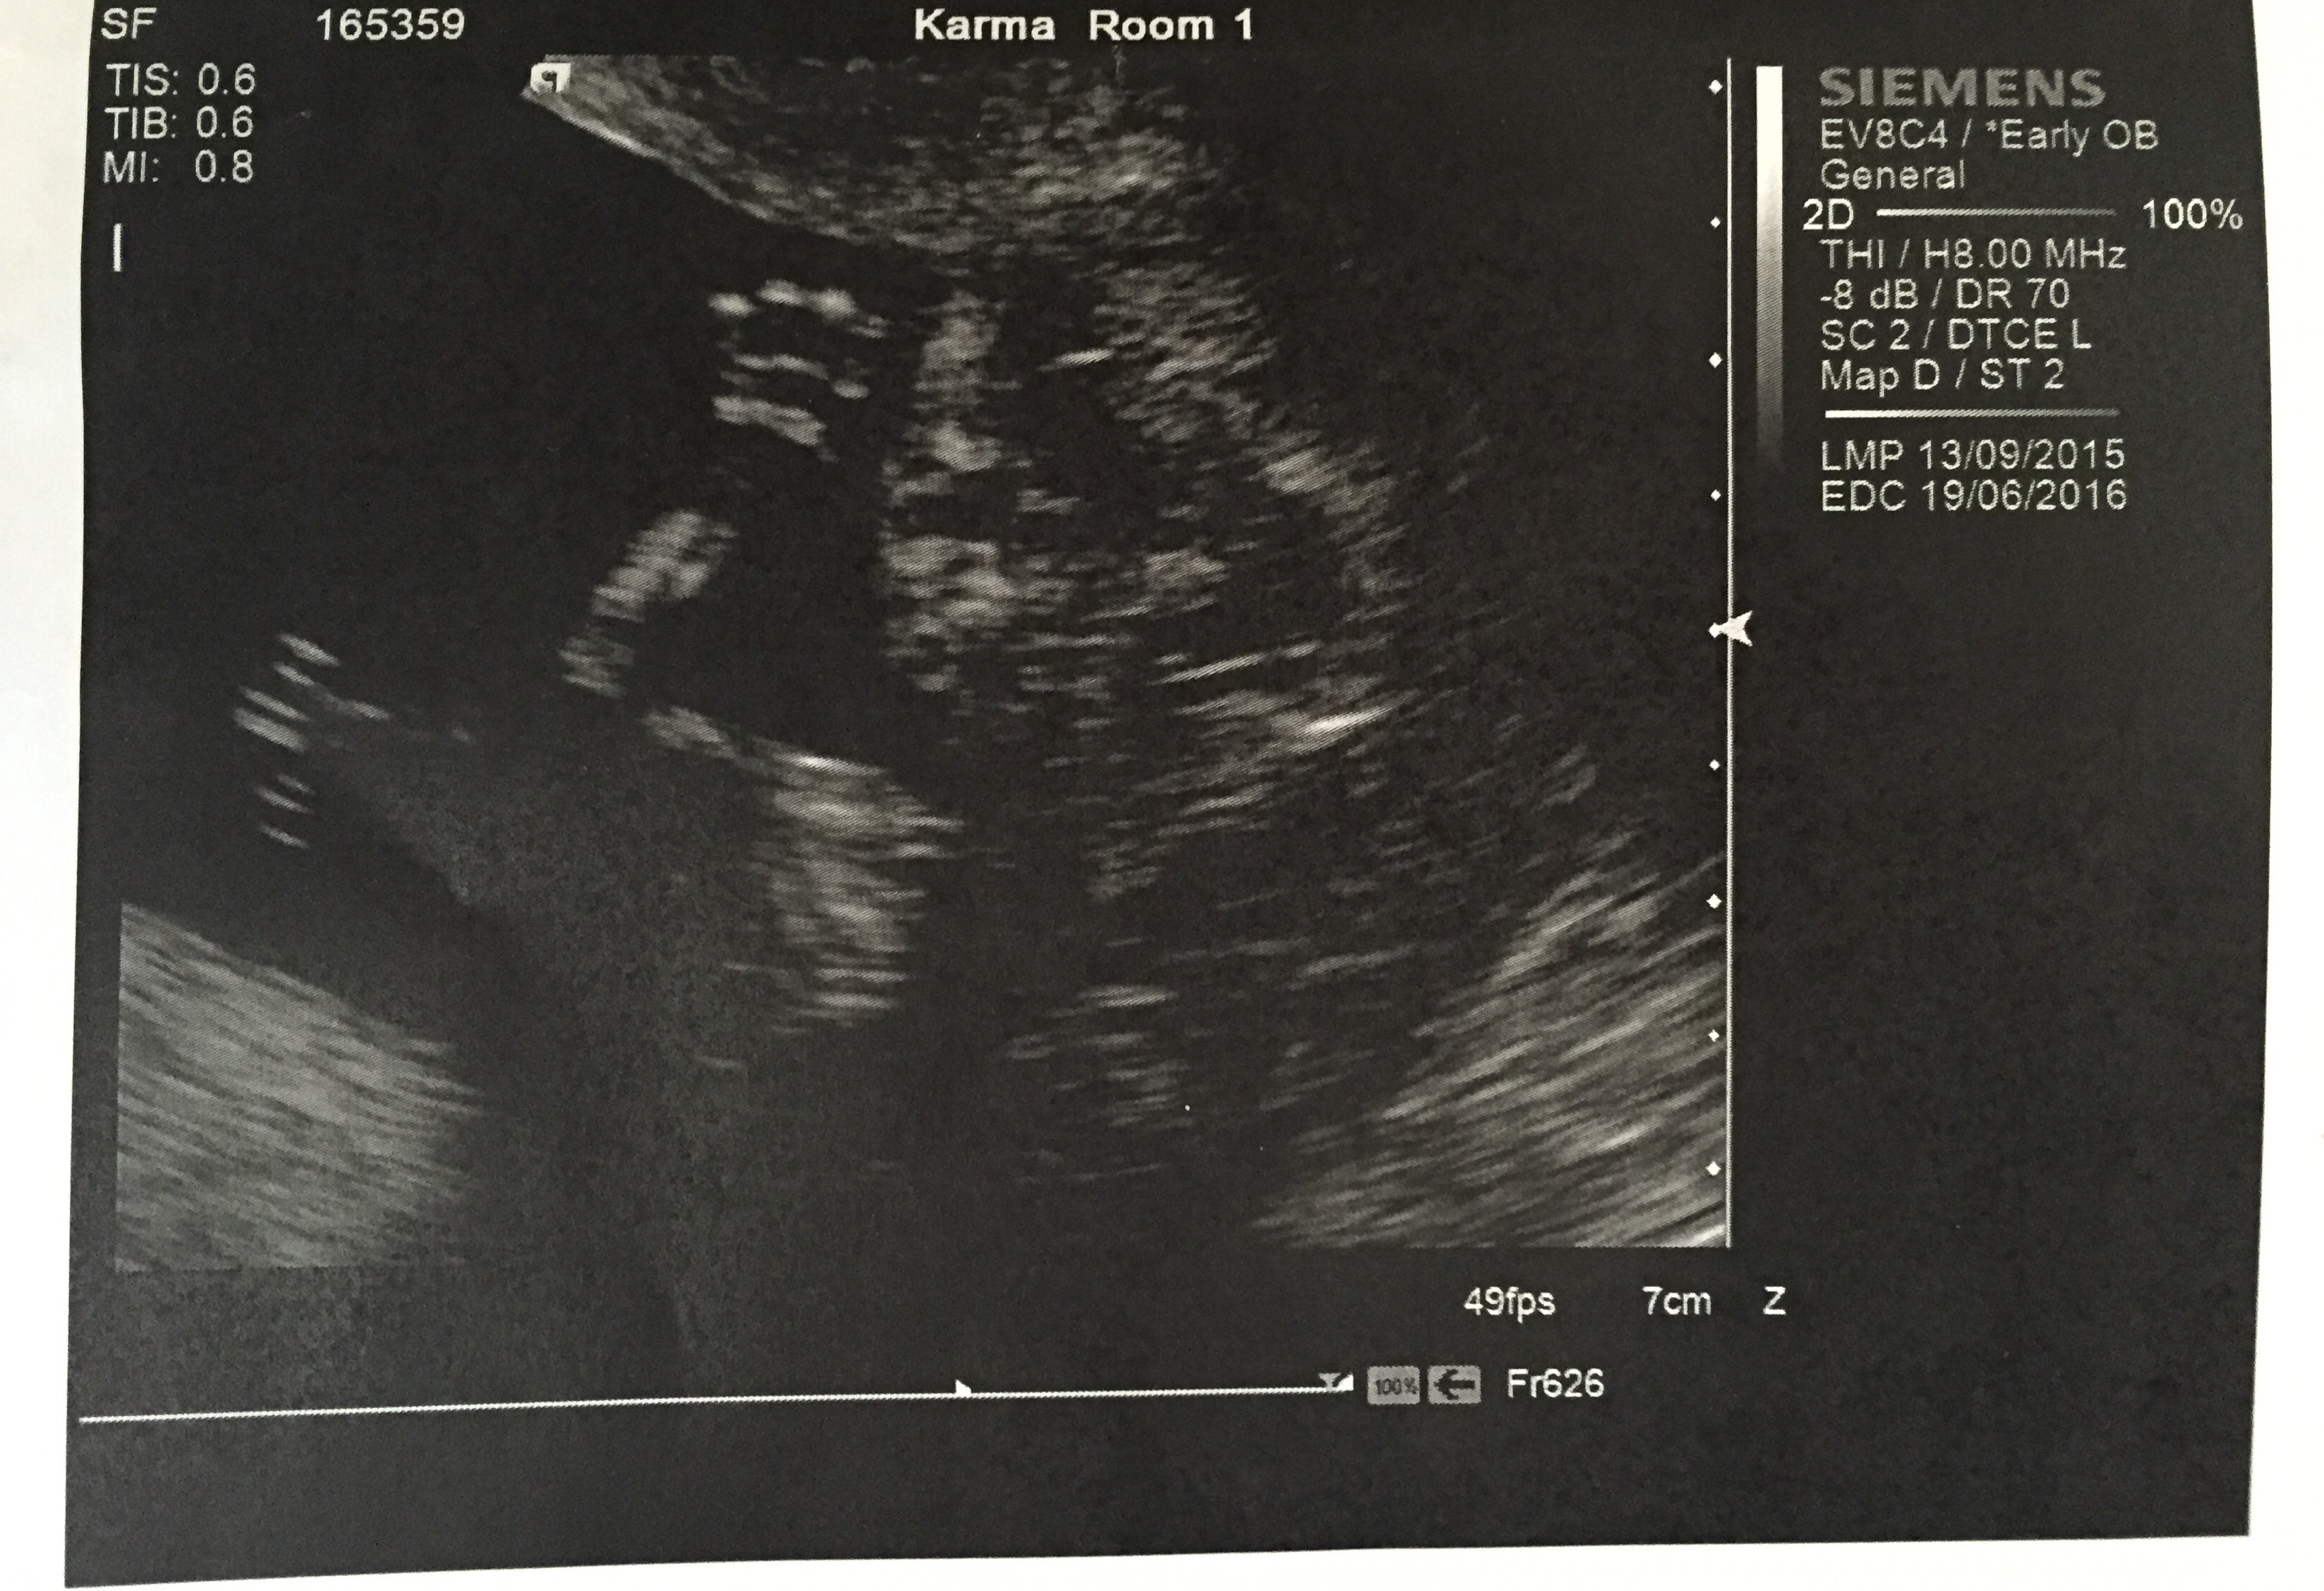

14 weeks 1 day. My Dr at my exam last week thought I felt further along, so we had this as a dating ultrasound and I was right. So happy I got to see baby!